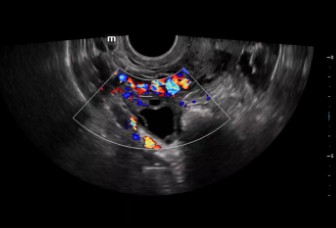

The Consona features new and concrete solutions, that efficiently help you to carry out smooth diagnoses for extensive type of patients. You will find highly powerful tools available on this series to keep you stay ahead in Obstetrics and Gynecology diagnosis.

Image Gallery